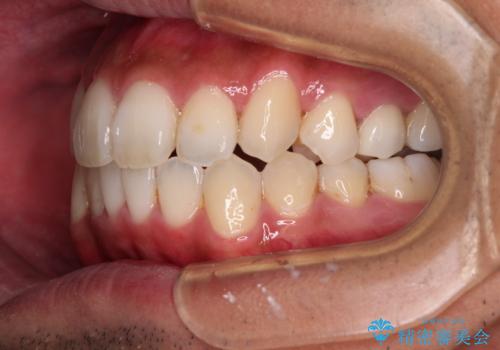

- 前歯のデコボコとクロスバイトを気にして来院された患者様です。

下顎の歯列弓に対して上顎歯列弓がやや小さく、側方の歯を中心にクロスバイトが見受けられました。

クロスバイトの改善は、インビザラインの場合歯髄壊死のリスクや咬み合わせが改善しきらないリスクがあるため、ワイヤー矯正をお勧めすることが多いですが、患者様の希望によりインビザラインにて矯正治療を行うこととしました。

奥歯の咬み合わせは接触が少なく物足りないように見えますが、患者様としては十分に咬むことができるとのことでした。